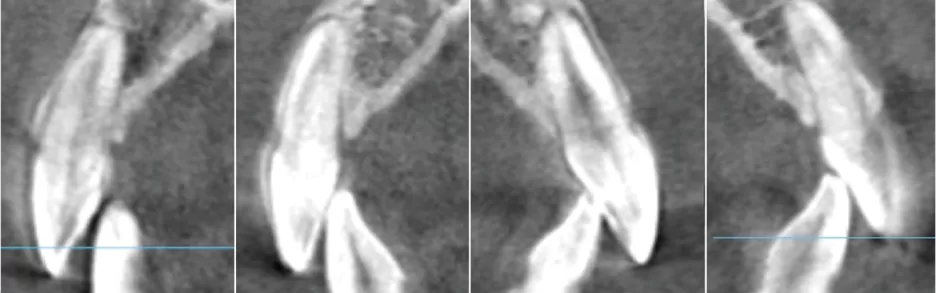

Centre de rotation intelligent S5

Rendre possible le mouvement précis des dents

Prévenir la fenestration des os et la déhiscence des os

Étape 0

Étape 7

Étape 28